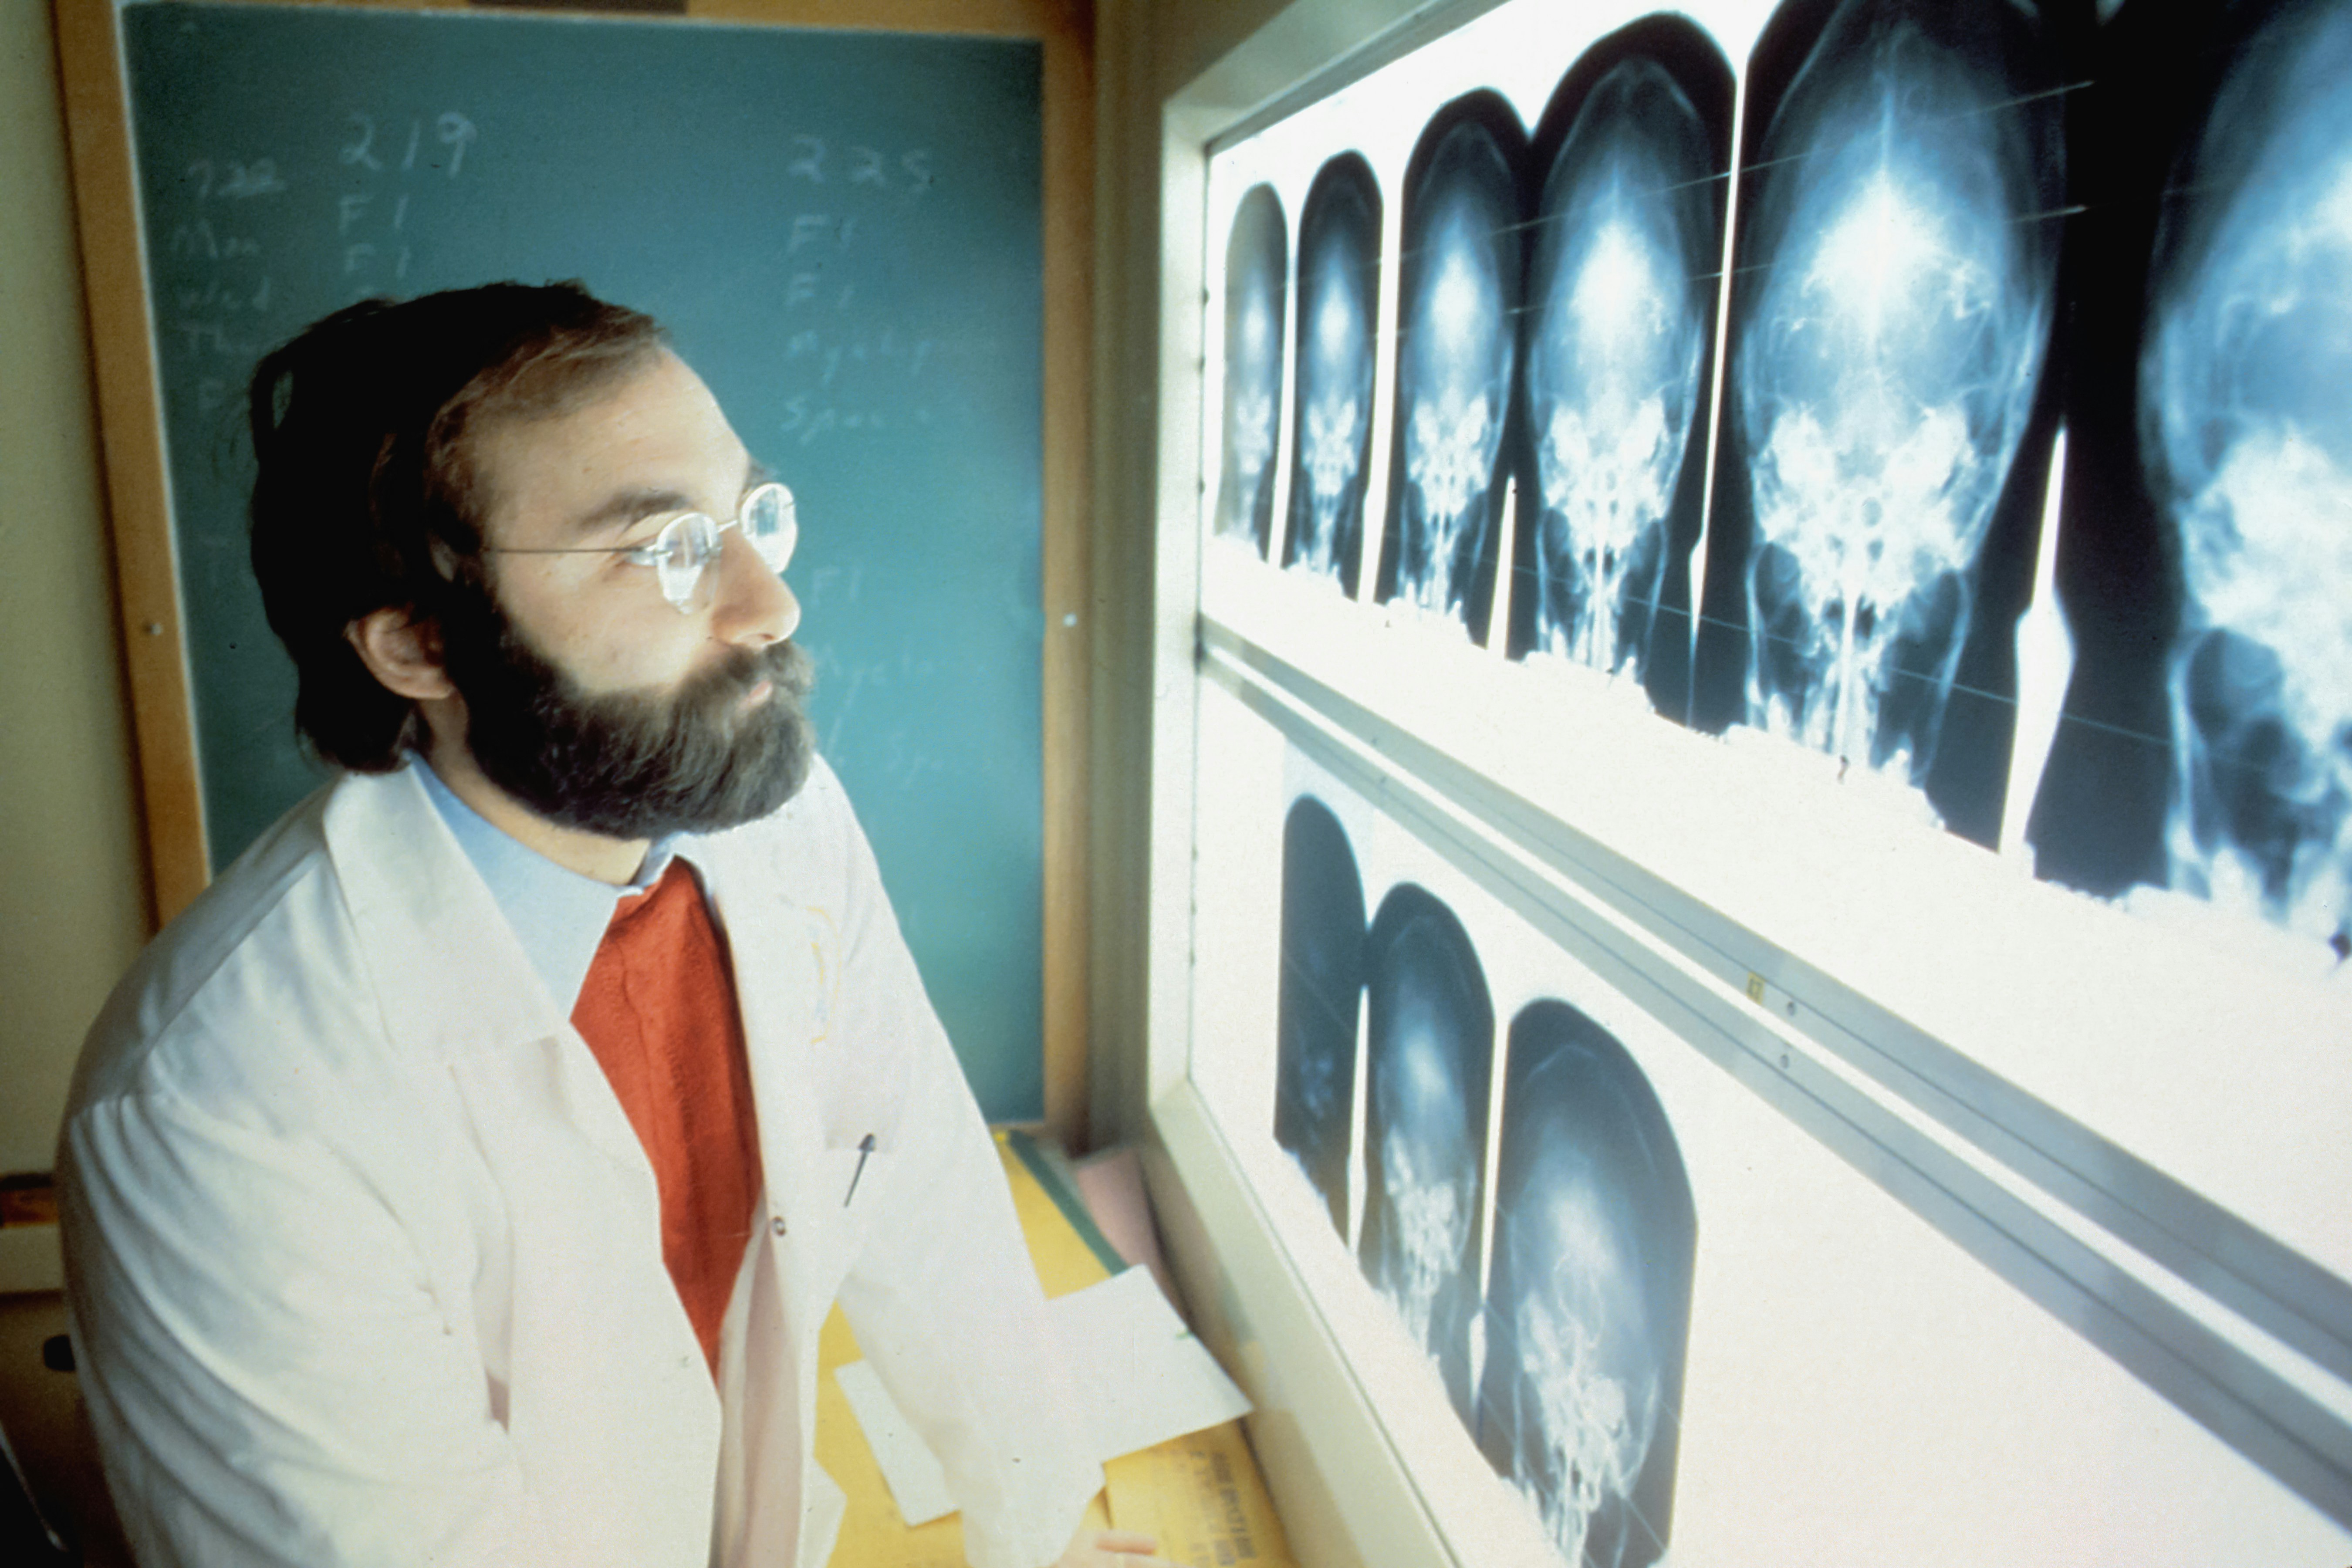

Bridging the gap between world-class medical expertise and global patients. High-precision surgery at lower costs than Western alternatives.

"Independent clinical audits ensure the highest surgical success ratios."